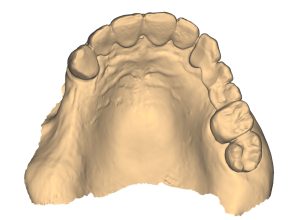

O diagnóstico padrão com escaneamento intraoral e CTCB (Fig. 3 escaner intraoral e Fig. 4 CTCB) mostrou disponibilidade óssea reduzida nas regiões 15 a 17, mas suficiente para a colocação imediata do implante. O dente 13, restaurado endodonticamente, apresentava uma obturação radicular que se estendia claramente além do ápice, juntamente com periodontite periapical. Em consulta com o paciente, foi decidido remover o dente.

O planejamento digital das posições ideais dos implantes em 3D, tanto do ponto de vista cirúrgico quanto protético, foi realizado usando o software de planejamento de implantes exoplan (exocad), com base em dados escaneados de CTCB e intraorais. O desafio era planejar a colocação imediata do implante na região 13 ao lado de dois implantes adicionais, garantindo a utilização ideal do osso disponível em termos de estabilidade primária suficiente para carga imediata por meio de uma restauração imediata provisória de longo prazo com uma ponte implantossuportada. Um implante (comprimento 10 mm, diâmetro 3,3 mm) foi posicionado exatamente na frente do seio maxilar na região 15 e o segundo implante (comprimento 8 mm, diâmetro 4,1 mm) foi planejado na região 17 (Fig. 6). As atenções do software e as indicações de distância de segurança foram particularmente úteis nesse processo.